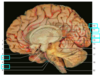

Label the arteries that supply A-C [3]

A = anterior cerebral artery (upper

and medial parts of the cortex)

(orange)

B = middle cerebral artery (lateral

areas of the frontal, parietal, and

temporal lobes) (white)

C = posterior cerebral artery (occipital

lobe and inferior parts of the

temporal lobe) (blue)